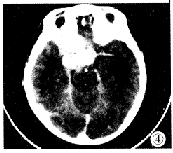

图4 与图3同一病人的颅脑CT增强扫描,肿块侵入颅内至鞍上及鞍旁。